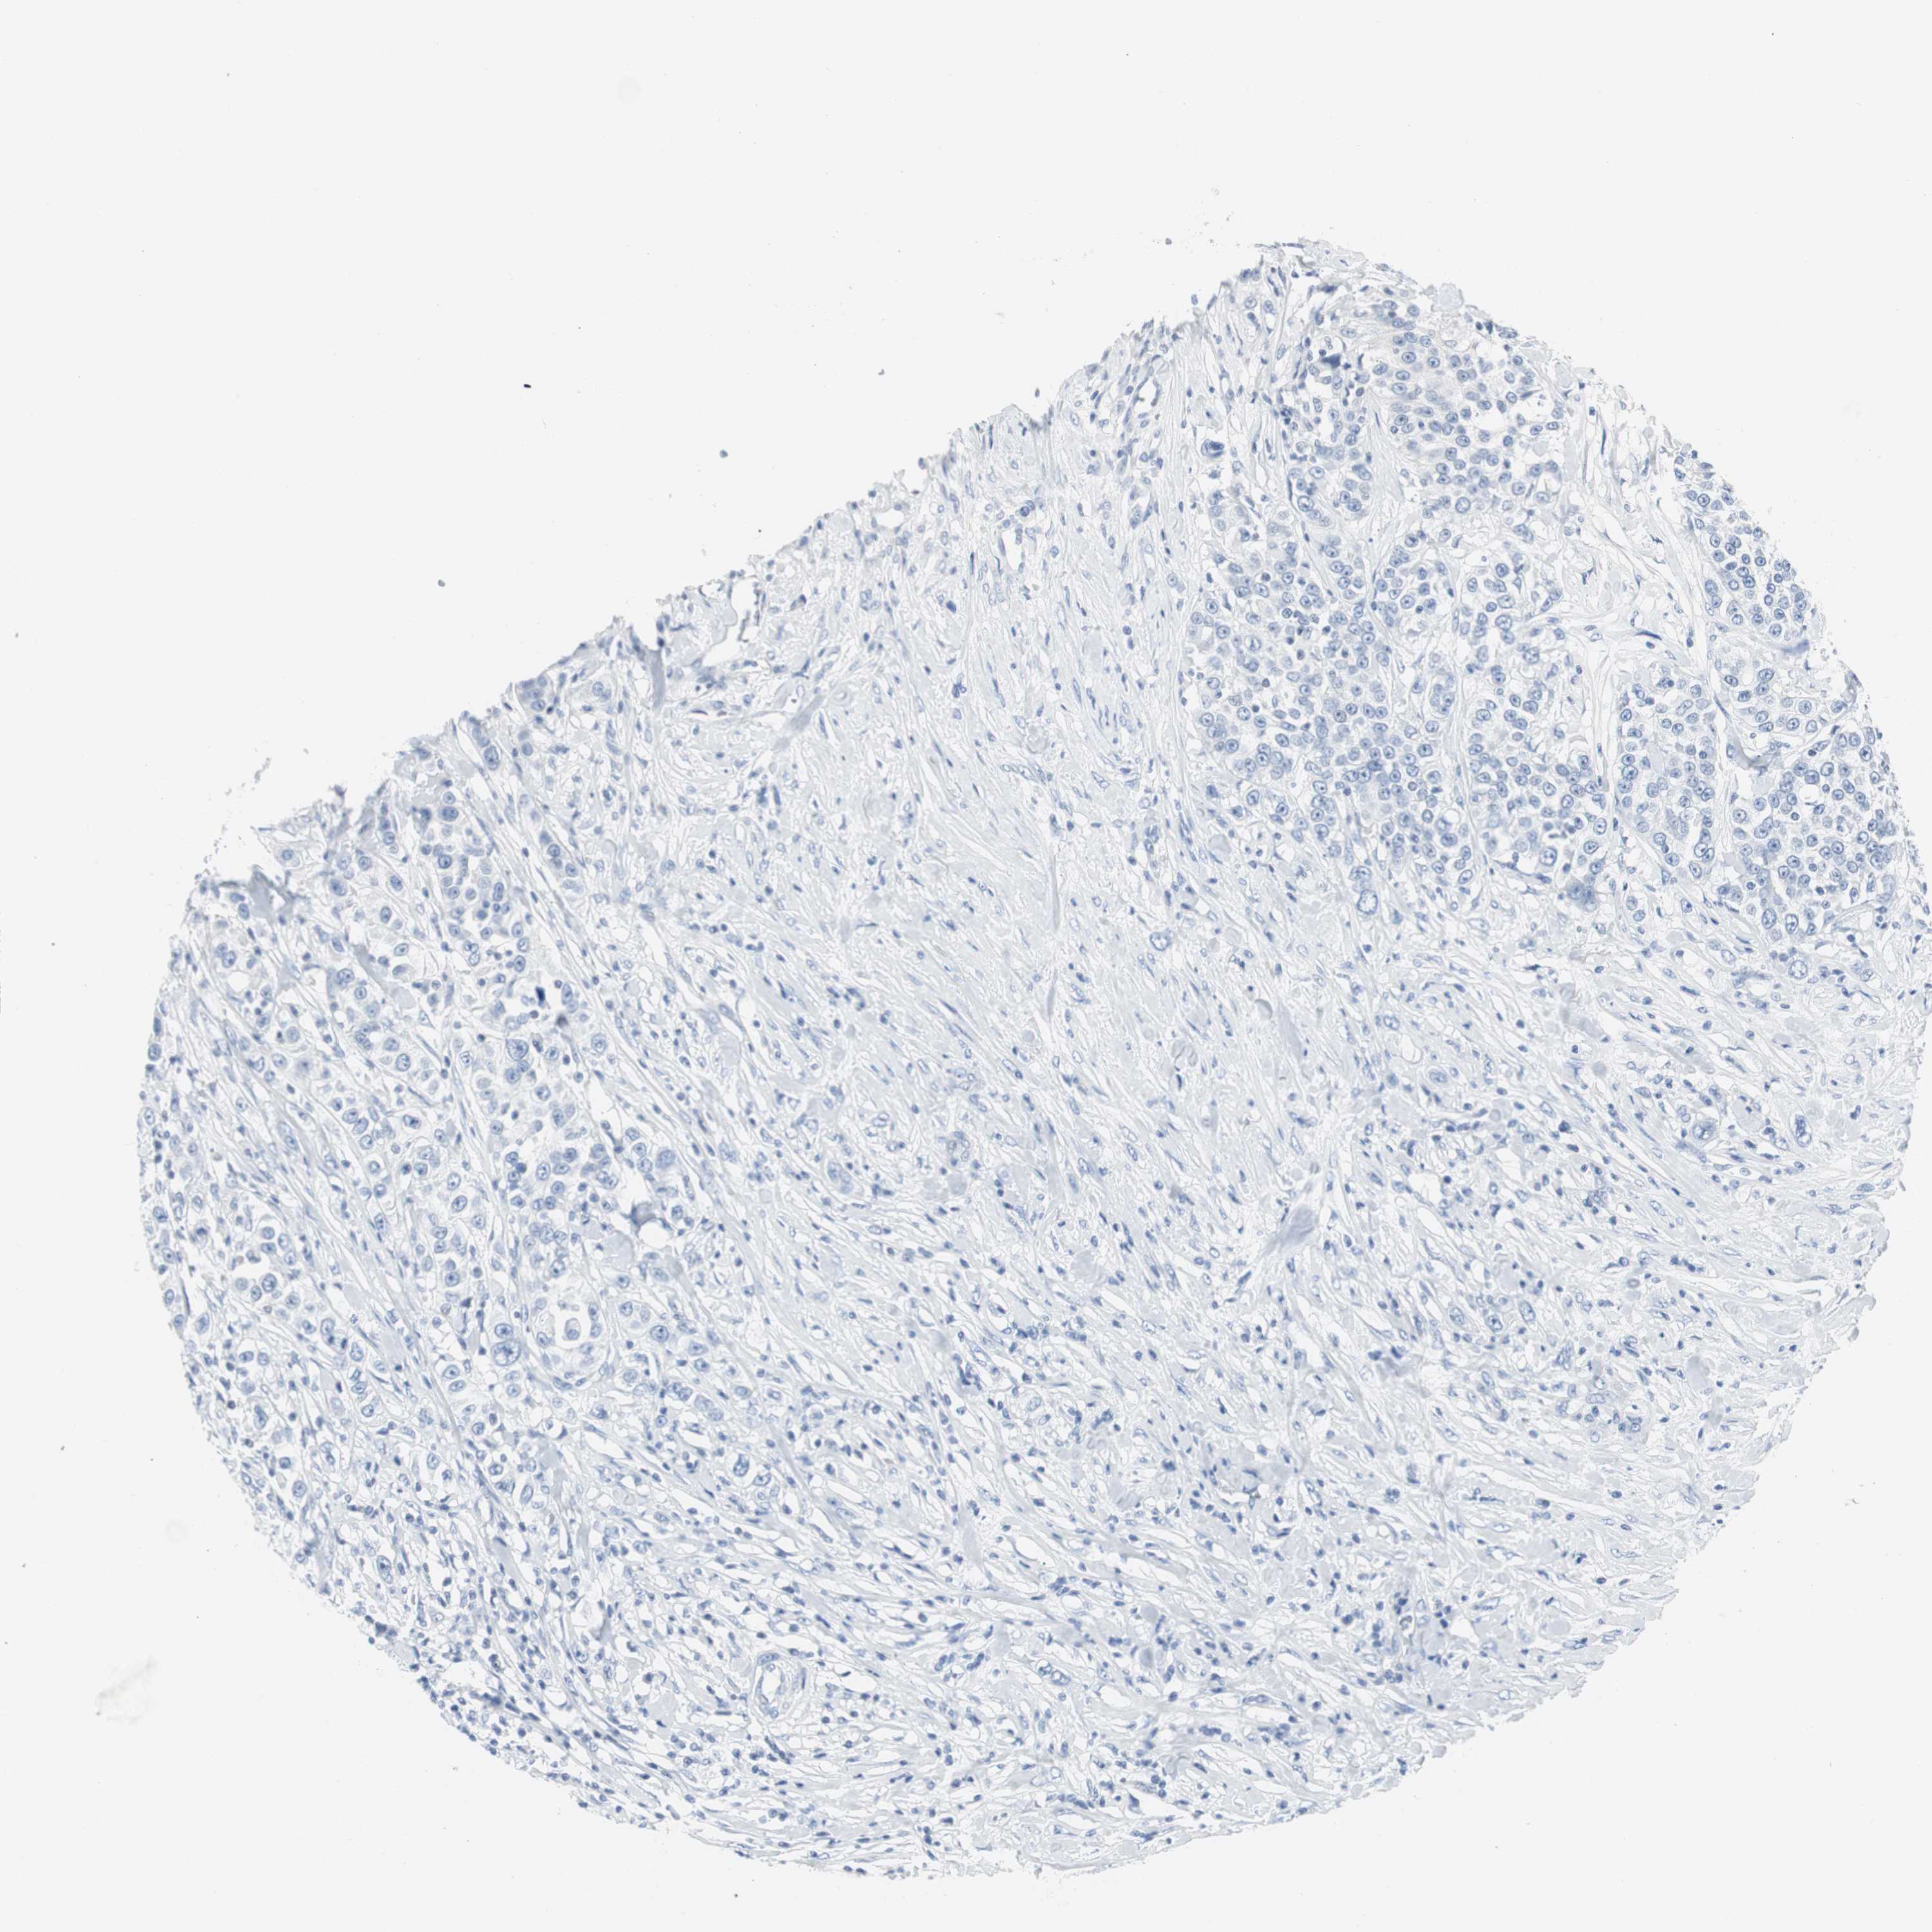

UROTHELIAL CANCER - Protein expressioni

A mouse-over function shows sample information and annotation data. Click on an image to view it in a full screen mode. Samples can be filtered based on level of antibody staining by selecting one or several of the following categories: high, medium, low and not detected. The assay and annotation is described here.

Note that samples used for immunohistochemistry by the Human Protein Atlas do not correspond to samples in the TCGA dataset.

Antibody stainingi

Antibody staining in the annotated cell types in the current human tissue is reported as not detected, low, medium, or high, based on conventional immunohistochemistry profiling in selected tissues. This score is based on the combination of the staining intensity and fraction of stained cells.

Each image is clickable and will lead to virtual microscopy that enables deeper exploration of all samples and also displays staining intensity scores, fraction scores and subcellular localization as well as patient and tissue information for each sample.

Antibody HPA013392

Antibody HPA015600

Antibody CAB004417

Staining

High

Medium

Low

Not detected

Intensity

Strong

Moderate

Weak

Negative

Quantity

>75%

75%-25%

<25%

None

Location

Nuclear

Cytoplasmic/membranous

Cytoplasmic/membranous,nuclear

Urothelial carcinoma, Low grade

Urothelial carcinoma, High grade